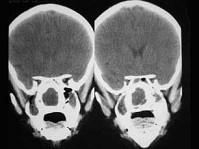

女,14岁,渐进性鼻塞2年余,右眼肿痛数月,CT如图所示,应诊断为 ( )

• A.筛骨骨化性纤维瘤

• B.筛骨骨肉瘤

• C.筛骨结核

• D.筛骨软骨瘤

• E.筛骨骨纤维瘤

答案: A